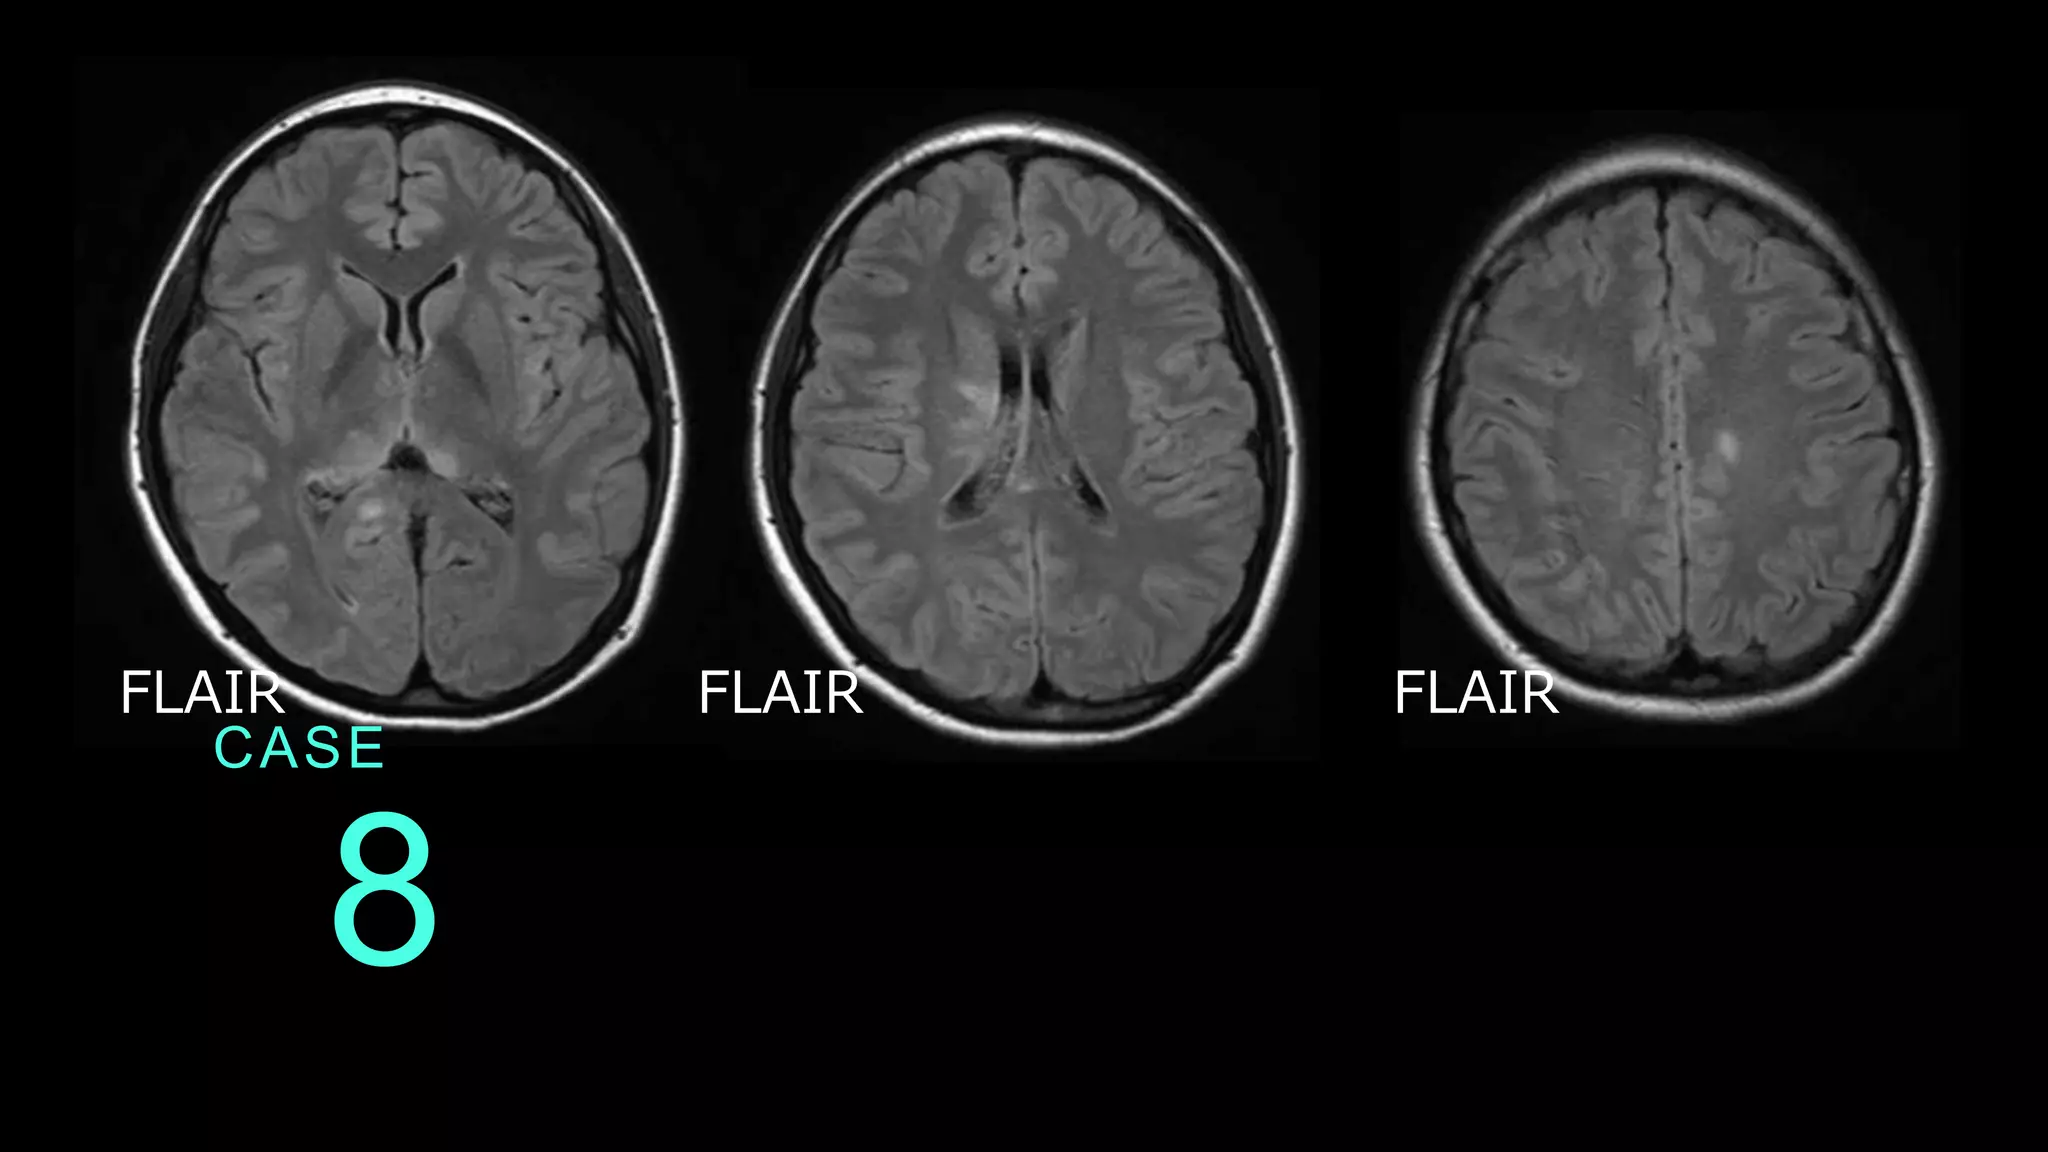

8 CASE FLAIR FLAIR FLAIR

8 CASE DWIでは信号変化がないので、FLAIRのみ提示。 基底核レベルのスライスで、左側脳室近傍の高信号変化 あり。放線冠レベルのスライスでも、右側脳室に沿った 高信号病変あり。前頭葉白質にも斑状高信号病変あり。

8 CASE コメント:多発性硬化症の症例。他の撮像条件で信号変 化が特になかったので、1つ提示するならFLAIRをみせ よう、という症例。